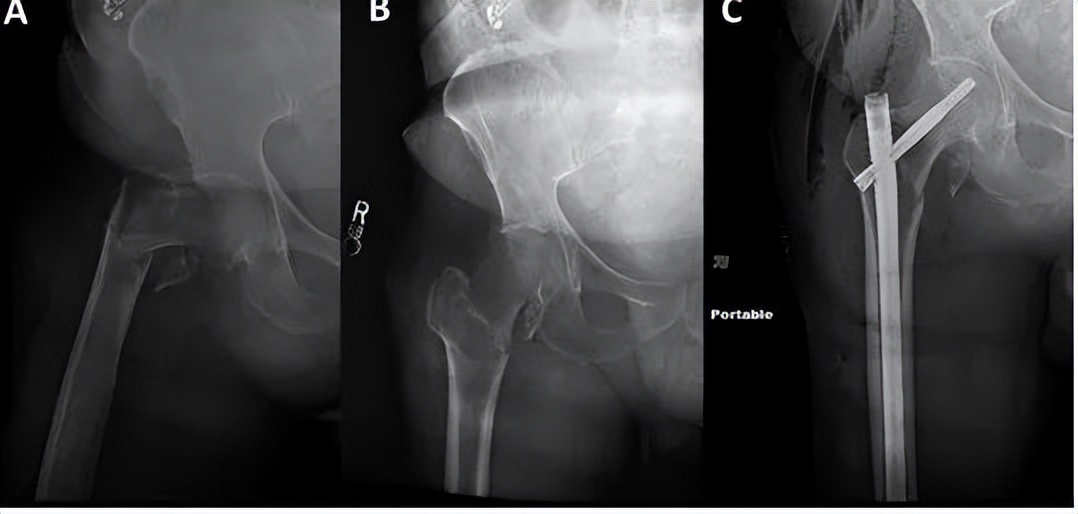

逆转子间骨折在复位和植入方面存在特别的挑战。需区分高能和低能粗隆部骨折,因为这些骨折的“表现”不同(下图)。虽然低能骨折可以在骨折手术台上通过闭合复位成功治疗,但高能骨折通常需要经皮或开放复位技术。

左侧髋关节侧位透视图显示尽管骨折手术台上有足够的牵引和旋转,骨折碎片仍有较大的移位。